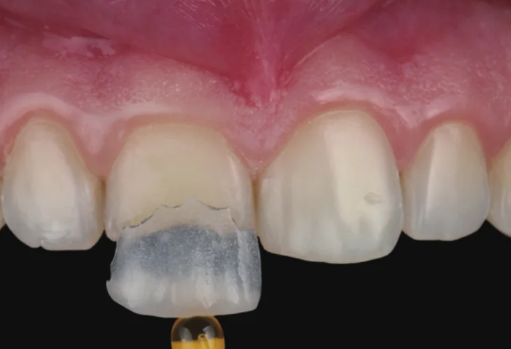

아랫니 라미네이트는 생각보다

까다로운 시술입니다.

아랫니는 혀의 움직임과 침의 영향을

많이 받는 부위라서 접착이 어렵고,

저작 시 강한 압력을 받기 때문에

탈락 위험이 높습니다.

20231107 아랫니 라미네이트 전

20231120 아랫니 라미네이트 후